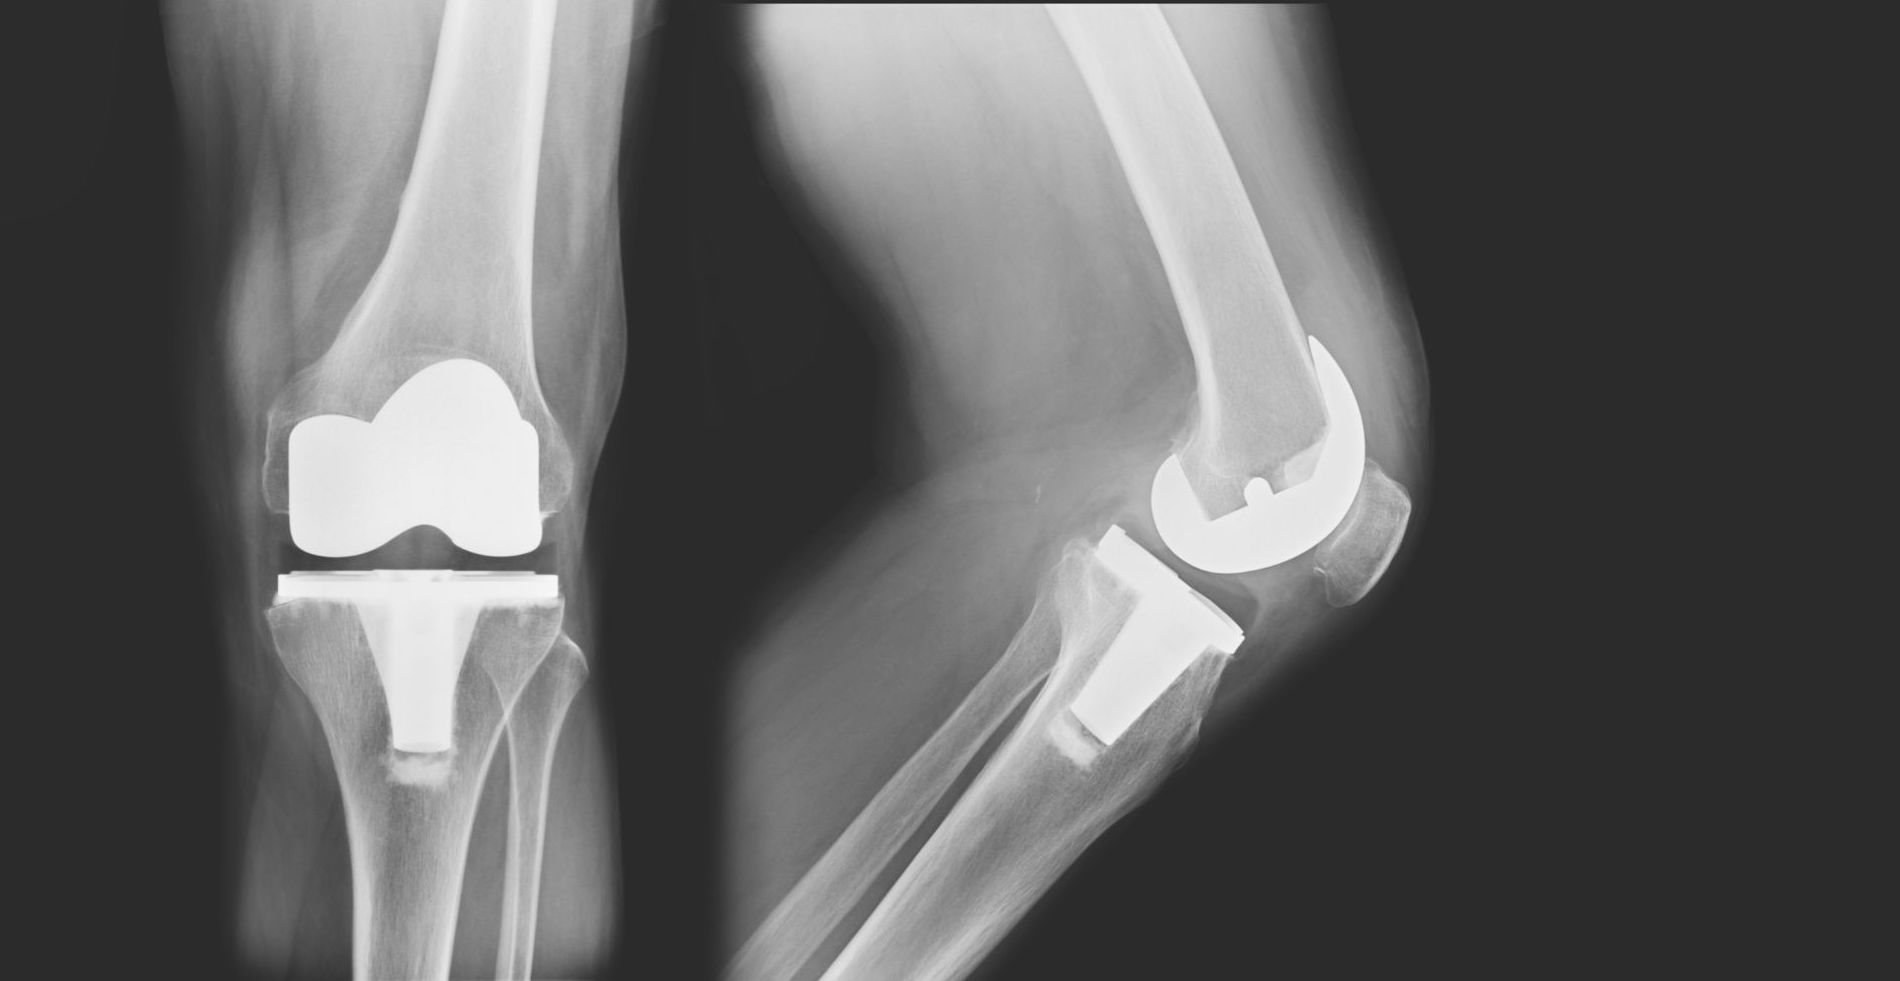

Types of knee replacement

Types of knee replacement Lupus And Knee Replacement most patients with sle do not present with inflammatory arthritis with effusion although up to 90% of lupus. if the surgery can be delayed (this is often called elective surgery), it is best to plan well ahead of time. the first studies to detail and compare the odds and incidence rate over three decades for arthroplasty, arthrodesis. Lupus And Knee Replacement.